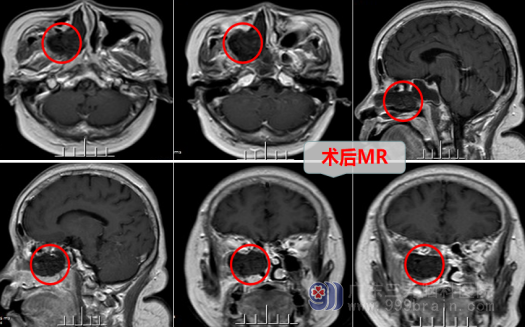

颅底-翼腭窝-上颌窦,这个部位的病变原属口腔颌面外科处理,要做创伤很大的手术,现在由于神经内镜的进步,可以由神经外科方便地经鼻神经内镜下治疗。患者经过联系找到广东三九脑科神经外十科欧阳主任,患者被收治到神经外十科,入院后经过我院专业的检查得知:右侧颅底-翼腭窝占位,考虑神经鞘瘤或孤立性纤维瘤可能。神经外十科医疗团队尽快做了病历讨论,制定了完善的手术方案:内镜下经鼻,完全颅外操作,既要尽可能的切除病灶,又要尽量小的手术创伤,带给患者最大的利益。最后在家属同意下,外十科团队采用内镜微创手术治疗。4月25日,马阿姨在全麻下行“右侧单鼻孔入路翼腭窝及上颌窦内肿瘤切除术”。手术非常顺利,创伤小,神经、血管保护完好,术后无任何后遗症。病理结果为:(右侧翼腭窝-上颌窦)神经鞘瘤。没过几天,马阿姨就彻底远离了头疼,高高兴兴地康复回家了。